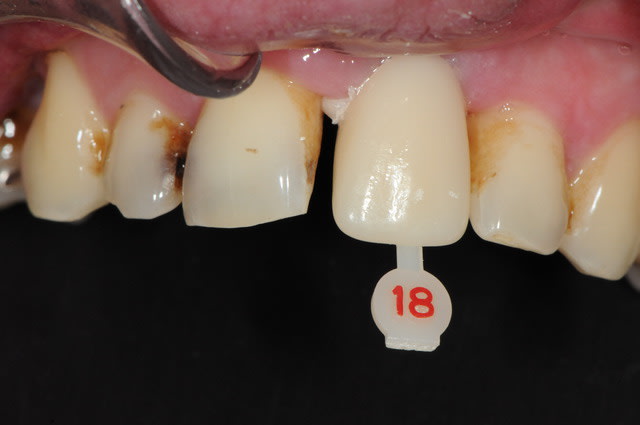

Dans le cas présenté, les images sont sur-exposées, couleur fade.

Need better white balance on your picture.

Set your camera white balance to flash, and reduce your flash output.

Avec un parodonte épais comme celui-ci, former la gencive n'est pas trop difficile.

With a gum biotype like this on, manipulating the gum is not very difficult.

Il y a aussi un gummy-smile et un sourire inversé, dommage après tant de couronnes.

The final result is a gummy smile with reverse smile line...too bad after all those crowns. A simple perio surgery could have give better result.